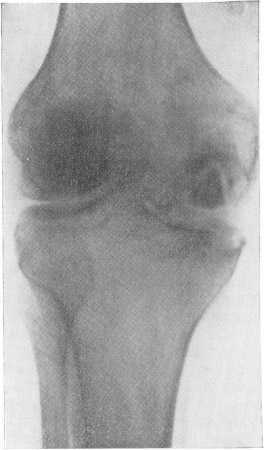

туберкулез коленного сустава

Рис. 20. На фото туберкульоз колінного суглоба. Під хрящем видно велику ділянку некрозу (секвестр). Виростків стегнової і великогомілкової кісток зруйновані.

туберкулез коленных суставов

Рис. 21. На фото туберкульоз колінних суглобів.